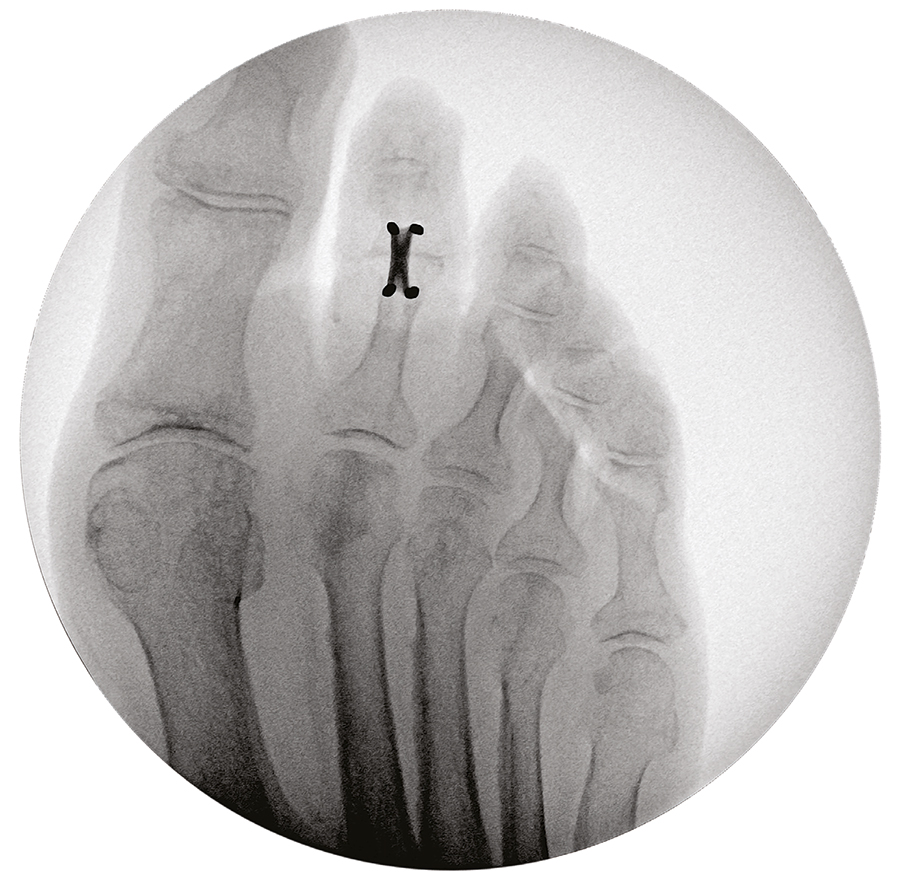

Once the DPS Hammertoe CCI is inserted into the bone and released from the Insertion Stick, the implant attempts to regain its original shape with converging legs thereby providing active continuous compression at the fusion site (Fig 3 and Fig 4). The implants do not require any external heating since they are already activated when preloaded on the insertion stick. The DPS Hammertoe CCI is not supposed to be reused after it has been discharged from the Insertion Stick because any processing, reprocessing, or mechanical manipulation may reduce the effectiveness of the implant. If for any reason the implant must be removed from the bone during the operation, then it must be replaced by a new one.

Since the DPS Hammertoe CCI is an extramedullary implant, it offers higher rotational stability than intramedullary implants (Fig 5). Its design with the four legs orthogonal to the bone axis and the active compression feature are beneficial for the distraction resistance (Fig 6).